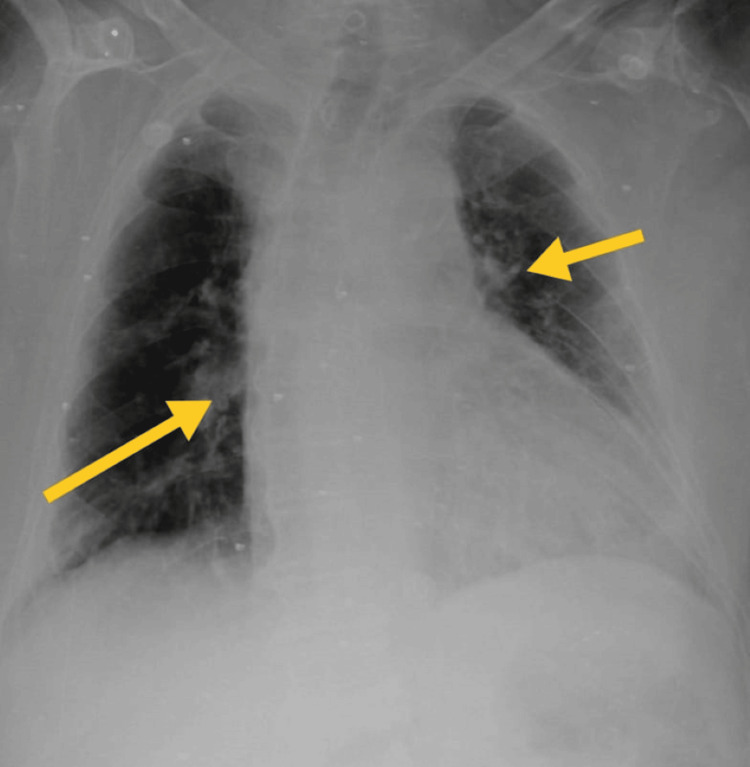

Figure 2. Thoracic radiography on 14th October 2023.

The yellow arrow shows homogeneous opacity in the left middle lung field, the lower lung field, and the right lower lung field.

ICU mobility scale [10], CURB-65 score for pneumonia severity [11], and X-ray grading scores [12] were used to assess patient progression. Tables 7, 8 show the outcome measures of the patient. In the inpatient department, every week, follow-up was taken to monitor the patient's condition. After discharge, the patient continued exercising at home and came back after two weeks for follow-up. Figures 2, 6, 7 show the X-ray, which is mentioned in Table 8.

Table 8. Thorax radiological findings were used as the outcome.

| On 14th October 2023 (day one) | On 22nd October 2023 (day seven) | On 30th October 2023 (Day 14) |

| Homogeneous opacity in the left middle and lower lung fields, cavitary lesion in the apical region, and obscured diaphragmatic outline and bilateral costo-phrenic angle in the left lung. | Heterogeneous opacity, prominent bronchovascular marking, mucoid impaction in dilated bronchi, branching opacities in bilateral lungs, and mild cardiomegaly. | Mild cardiomegaly with mild mucoid impaction in the bronchi. |